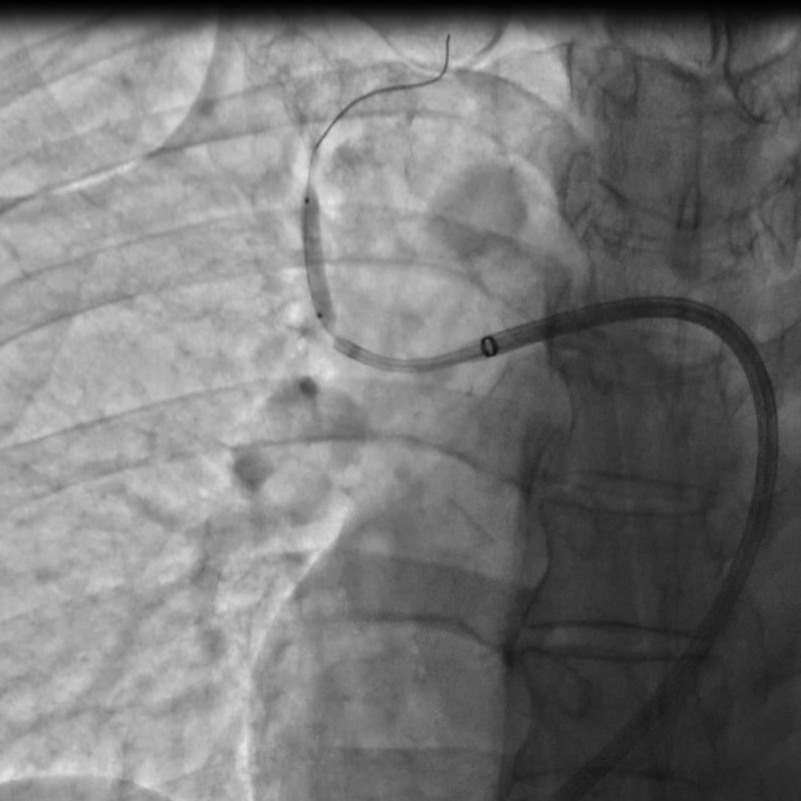

球囊扩张次全闭塞病变处

手术由心脏中心主任马翔、副主任医师吕文魁及戴远辉完成,团队分别依次对患者右肺动脉A10段、A5段、A1段行球囊扩张,先用2.0mm的球囊以6—12atm扩张,再使用3.0mm的球囊逐级扩张,球囊扩张后患者胸闷症状即刻好转,术后8小时已下地行走,目前各方面生理指标达到预期,即将出院。